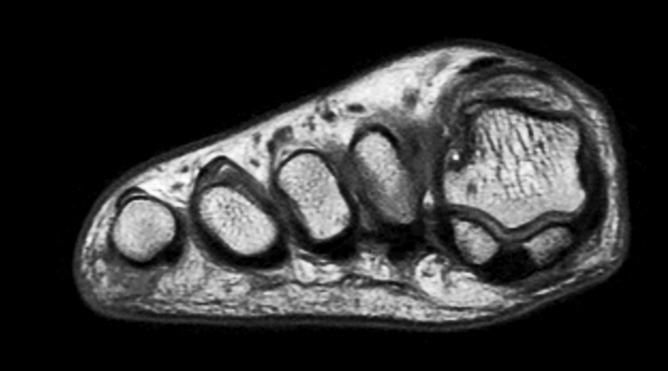

Sagittal PDw mDIXON TSE  (water only)

-